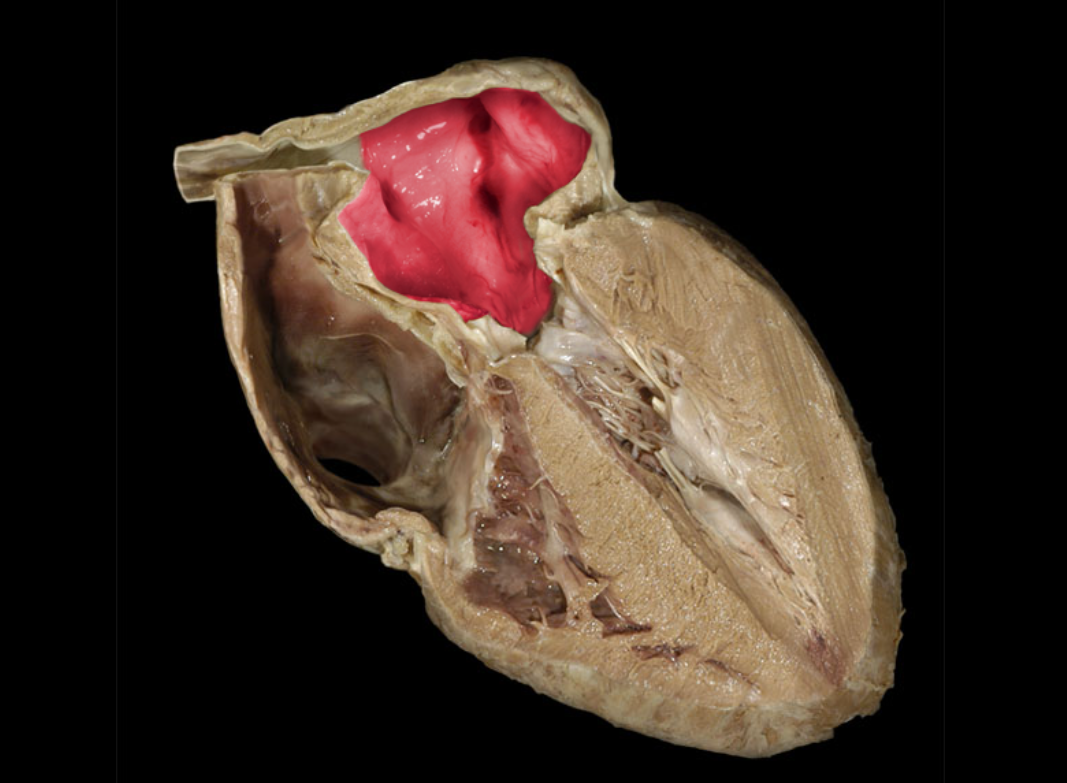

The structure at the tip of the arrow contains

deoxygenated blood of the pulmonary circuit

The auricles are flap-like projection off of the___and serve to increase their blood volume.

atria

Left auricle

Right auricle

Left atrium

Left auricle

Right atrium

Right auricle